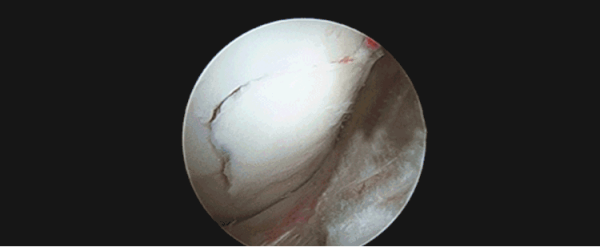

膝关节半月板损伤导致关节软骨磨损

关节软骨损伤